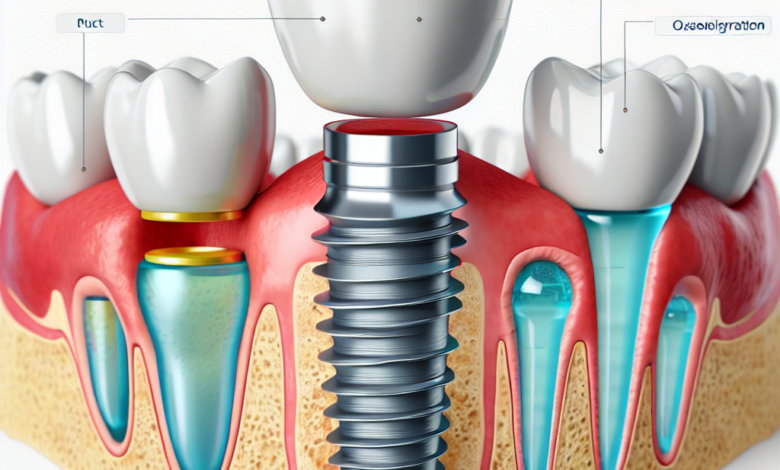

During the first surgical phase, the titanium implant is inserted into the jawbone. This procedure is usually performed under local anesthesia, ensuring comfort. Once the implant is placed, your body begins healing and integrating the implant into the bone in a process called osseointegration.

The healing phase can take several months, during which the bone grows around the implant, creating a secure anchor. This is crucial for the strength and longevity of the implant.

4. Abutment Placement

Once healing is complete, an abutment (a connector piece) is attached to the implant. This is where the replacement tooth or teeth will be anchored.

5. Crown Creation and Placement

Finally, a custom-made crown is created to resemble your natural teeth, which is then cemented onto the abutment. Your dental professional will ensure that the color and shape match your surrounding teeth.